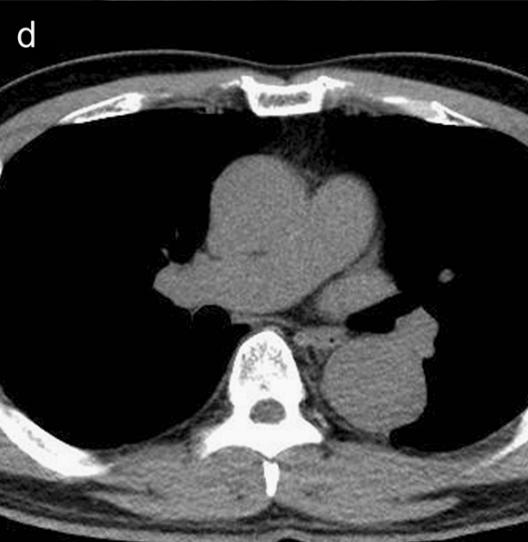

下图的胸部CT平扫,有什么致命的问题?

血管壁钙化啊,老年人很常见啊,

注意,看下面,钙化在血管的里面,不是在管壁!难道是血液钙化了?血液钙化?

这不是血液钙化,这是主动脉夹层导致的血管钙化内移!血液不会钙化,因为动脉夹层,导致钙化的内膜被压迫进入血管!

增强CT一看,就一清二楚了!

CT这么模糊,平扫怎么看主动脉夹层?

不着急!仔细看,血管里面的“血液”居然钙化了!这叫血管钙化内移,要警惕主动脉夹层!有研究发现,血管钙化内移诊断动脉夹层的特异性高达90%。

用箭头标记了,并且是增强CT,这是主动脉夹层!